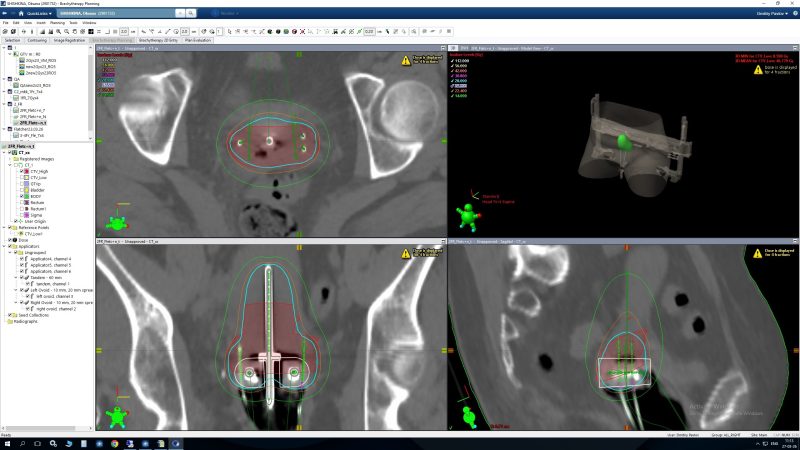

Дозиметрическое планирование только ICB Дозиметрическое планирование ICB/ISB

• Подавляющее большинство пациенток с гинекологическими заболеваниями получают внутриполостную брахитерапию (ICB), однако гибридная брахитерапия, включающая внутриполостную (ICB) и внутритканевую (ISB) компоненты, рекомендуется пациенткам, у которых применение ICB приводит к неоптимальному распределению дозы. ISB следует рассматривать у пациентов с обширным поражением параметрия, крупными первичными опухолями, а также при узком или дистальном поражении влагалища.

Данные исследований демонстрируют преимущество в локальном контроле у пациенток с крупными опухолями шейки матки, получающих гибридную ICB/ISB, по сравнению с применением только ICB.